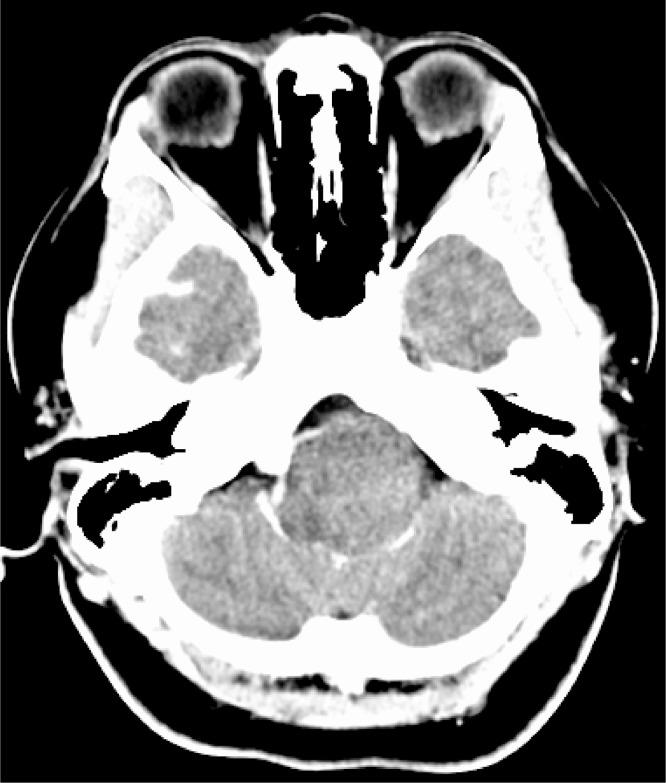

Neurenteric cysts are uncommon, benign lesions that are rarely located intracranially. These cysts are likely due to aberrant embryologic development of the notochord. Clinically, neurenteric cysts may present with symptoms of mass effect, or they can be asymptomatic and incidentally discovered. Imaging features of neurenteric cysts have significant overlap with other intracranial cystic lesions, which can make diagnosis difficult. We present a case of a 35-year-old female with a histopathologically confirmed neurenteric cyst in the premedullary and left cerebellomedullary cistern, with associated symptoms of headache, dizziness, tinnitus, and dysphagia. The patient underwent surgical resection, with improvement in symptoms. We present a review of literature, and a discussion of typical features of multiple intracranial cystic lesions. We hope to promote accurate preoperative diagnosis, to allow for appropriate surgical technique to reduce the risk of recurrence.